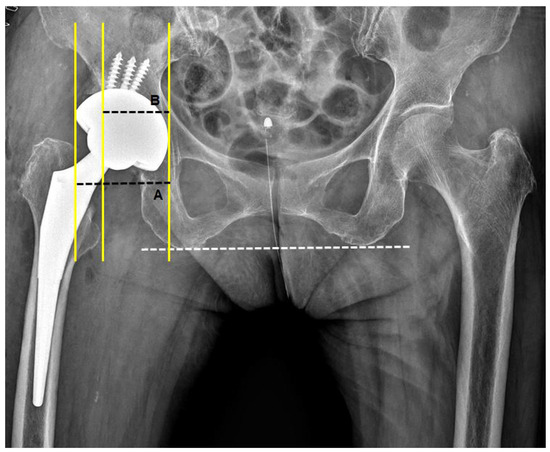

2.4. Cup Position and Fixation

2.5. 2D-Based Measurement of Host Bone Coverage from Plain Radiographs of the Pelvis